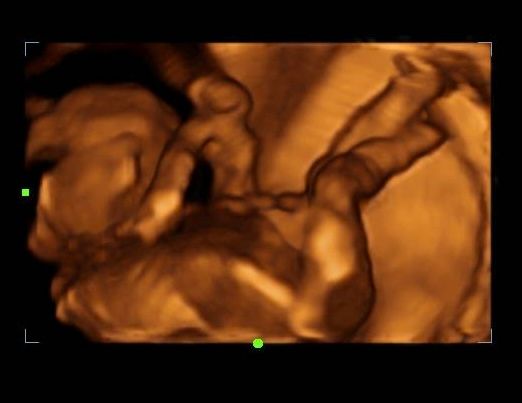

2d, 3d,4d & HD live

Enjoy a private, affordable ultrasound from the comfort of your home, perfect for moms between 7–41 weeks. Share the moment with loved ones by connecting directly to your TV for real-time viewing in 2D, 3D, or 4D. Ideal for baby showers or gender reveal parties!